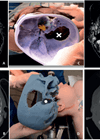

The utilisation of three-dimensional printed models in skull base surgery

As technology improves, there are new ways to assist with surgeons when it comes to training and preparing for surgery. Barbara Anne Thomson and Georgios Kontorinis highlight how 3D printing can help with the understanding and surgical planning for complex...